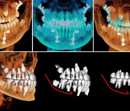

Three dimensional imaging for dental implant placement provides for precise diagnosis and control of implant placement. Dr. Janice Babin has invested in the advanced digital imaging equipment needed to produce 3-dimentional views to enhance the accuracy and safety of placing implants.